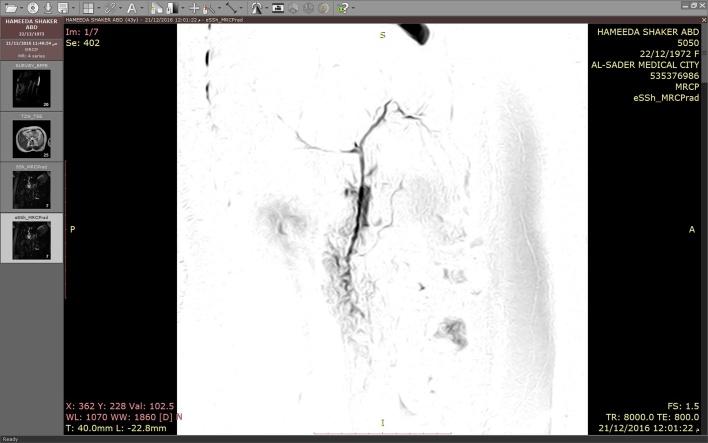

一名43岁女性,有4个月上腹部疼痛病史,伴有恶心和呕吐。与消化不良症状相关,进食高脂肪食物后症状加重。临床上,考虑为胆结石疾病。腹部超声显示胆囊缩小,有多个结石,胆囊壁厚度正常,因此根据检查结果临床诊断为胆石症。她接受了腹腔镜探查,结果显示胆囊窝内无胆囊。

在常规影像学检查中胆囊显示不清时,应考虑胆囊缺如的可能。超声检查依赖操作人员,我们不能仅依赖单次检查结果,甚至不能仅依赖同一人进行的多次检查结果。避免不必要的手术探查,因为这可能有风险。腹腔镜胆囊切除术中未见到胆囊具有挑战性,除非确定胆囊存在,否则不应转为开腹手术。

Gallbladder Agenesis: Report of a Preoperative Diagnosis With Magnetic Resonance Cholangiopancreatography.

胆囊缺如:一例磁共振胰胆管造影术前诊断报告